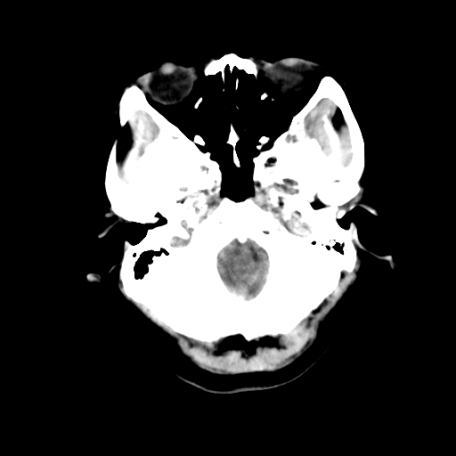

以下是引用深泽交通医院在2009-8-7 12:18:00的发言:[br]有壁结节,考虑囊变型胶质瘤

以下是引用帅河马在2009-8-7 13:50:00的发言:[br][quote]以下是引用深泽交通医院在2009-8-7 12:18:00的发言:[br]有壁结节,考虑囊变型胶质瘤

以下是引用卜一在2009-8-7 15:50:00的发言:[br]囊变性脑膜瘤!支持!

以下是引用随光逐影在2009-8-7 15:58:00的发言:[br]考虑左侧顶叶胶质瘤,不排除左侧镰旁脑膜瘤;建议行进一步检查。